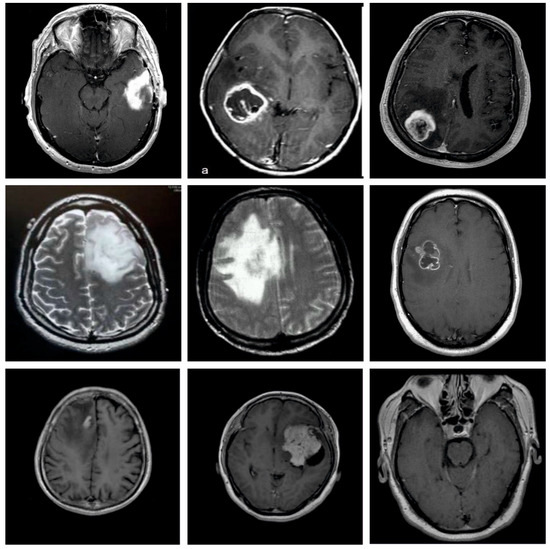

In this study, the performance validation of the EADL-BTMIC model is carried out using the Figshare dataset [24]. The details related to the dataset are shown in Table 1. A few sample images are illustrated in Figure 3. The dataset holds 3064 T1-weighted contrast-enhanced images with 3 kinds of BT. The dataset includes 708 images in the Meningioma class, 930 images in the Pituitary class, and 1426 images in the Glioma class. In this study, the experimental validation occurs in two distinct ways by splitting the dataset into two aspects based on the size of the training and testing data: 80% of training with 20% of testing data and 70% of training with 30% of testing data. The proposed model is simulated using Python 3.6.5 tool. The parameter settings are given as follows: learning rate: 0.01, dropout: 0.5, batch size: 5, epoch count: 50, and activation: ReLU.

Figure 3. Sample Images.

Applsci 12 07953 g003